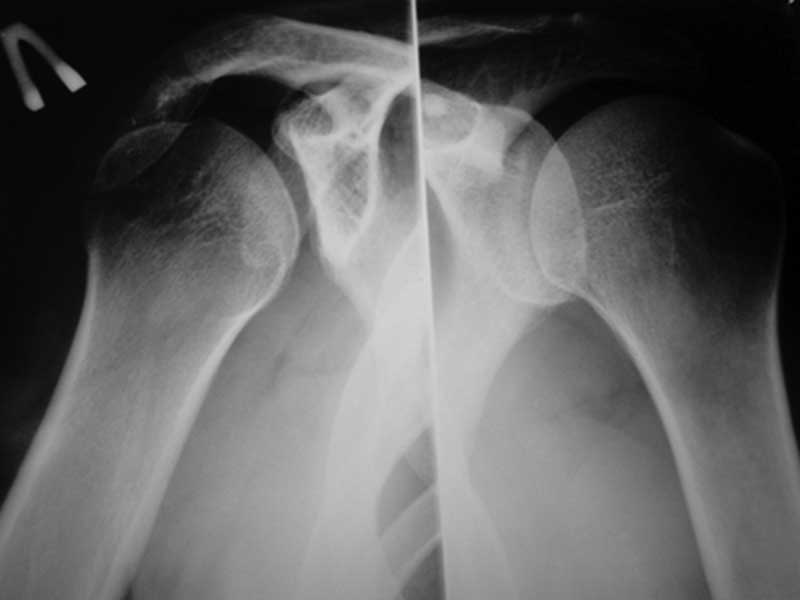

Уважаемые коллеги!Требуется ваша помощь. На консультацию обратился пациент 30 лет с жалобами на ограничение активных движений в левом плечевом суставе. Пассивные – в полном объеме. Со слов – имела место некая родовая травма. К тому же отмечается незначительный дефицит иннервации n.radialis (снижение «силы» разгибателей-сгибателей в кистевом суставе и отведения 1 пальца; неврологи никакого специфичного лечения не назначают). Также имеется контрактура локтевого сустава: сгибание в полном объеме, разгибание 150 градусов, супинация в пределах 7 градусов. Функция конечности в принципе устраивает. Скелетных травм в анамнезе нет. Вопрос: есть ли смысл заниматься какими-либо реконструкциям на плечевом суставе и как можно улучшить функцию скомпрометированных суставов? Заранее всем благодарен

Уважаемый Михаил, у Вашего пациента вероятнее всего "родовая травма" была скелетной, т.е. во время родовспоможения произошел эпифизеолиз дистального эпифиза плечевой кости. Клинически это проявляется некоторым непродолжительным ограничением подвижности в конечности, консолидация (учитывая возраст) проходит достаточно быстро (7-10 дней). Бывает, что при выписке из роддома ребенка уже ничего не беспокоит. Имеющийся на снимке локтевого сустава варус дистального метафиза плеч кости может быть результатом такой травмы. Что касается неврологии, при подобной травме может произойти повреждение лучевого нерва, но это как правило следствие больших смещений эпифиза (заметили бы сразу). Второй вариант - роды столь травматичны, что повредили и плечевое сплетение - проксимальный паралич Эрба, который либо не распознали, либо плохо лечили, в итоге ограничение амплитуды подвижности в плечевом суставе.